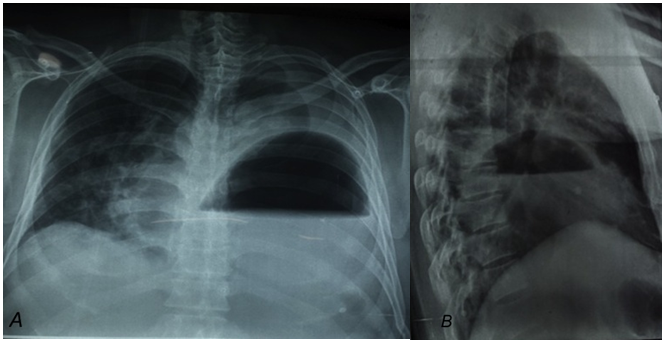

Figure 1A Postero-anterior thorax x-ray presenting gastric bubble occupying left thorax with liquid content and ipsilateral pleural effusion.

1B Lateral thorax x-ray showing stomach in left thorax with liquid content, no more intestinal loops observed.

A 54-year-old male presented at emergency room with respiratory insufficiency. His pathological background included Diabetes Mellitus 2 diagnosed 2years ago without medication and chronic alcoholism. He was drinking alcohol for previous 48hours, suspending ingestion 8hours before. He presented one day feeding intolerance and vomiting, adding itself respiratory insufficiency last two hours, reason why he came to hospital. At physical exam with Glasgow 15, dehydrated, not cooperative for respiratory distress, 110 beats per minute, arterial tension 90/50mmHg, 30 breaths per minute, without ventilation in left hemi-thorax and SO2 80% although supplementary oxygen with venture oxygen mask. Abdomen without hematomas or other superficial lesions, without acute abdomen signs but a correct evaluation can’t be accomplished by lack of cooperation. Emergency Department suspected tension pneumothorax after primary evaluation and practice a thoracic decompression with puncture obtaining 60cc of blood and intestinal material. An X-ray revealed a gastric bubble in left hemi-thorax with liquid content and ipsilateral pleural effusion (Figure 1A) (Figure1B). Laboratories revealed White blood cells 18000/mm3, neutrophils 92%, hemoglobin 13.7g/dL, Platelets 82000, Glucose 160mg/dL, Cr 1.4mg/dL. Gas Analysis reported pH 7.1 pO2 52mmHg, pCO2 22mmHg, HCO3 16mmol/L, BE ecf -14.5mmol/L, SO2 82%. Surgical department analyzed the case and suspected a diaphragmatic hernia with gastric incarceration, and perforation secondary to thoracic puncture. CT scan was not developed because septic shock was a contra indication and surgical management has been decided. Emergency laparotomy was developed for gastrointestinal perforation, finding a left postero-lateral diaphragmatic hernia with 9 cm of diameter, 300cc intestinal liquid in thoracic cavity and 90% gastric necrosis with 2mm perforation in the body (Figure 2). After reduction stomach does not presented reperfusion. Subtotal gastrectomy with Y-Roux gastro jejunum anastomosis and diaphragmatic hernioplasty with interrupted polypropylene stitches was developed without intraoperative complications (Figure 3). Patient persisted with septic shock and metabolic acidosis after surgery so their income was decided to intensive care unit. His evolution was torpid and after 7days in intensive care unit a minimal abdominal improvement was noted but unfortunately he developed pneumonia and died 7 days later.